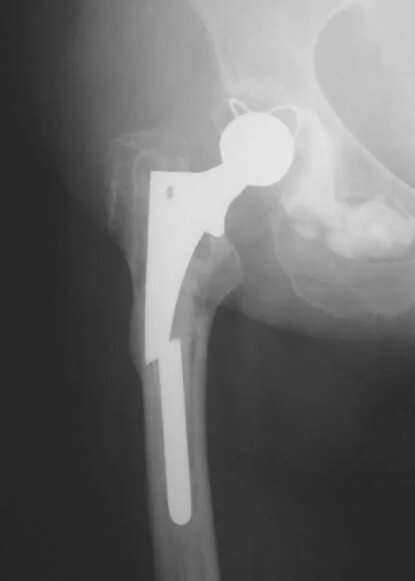

Эндопротезирование сроки тазобедренного сустава